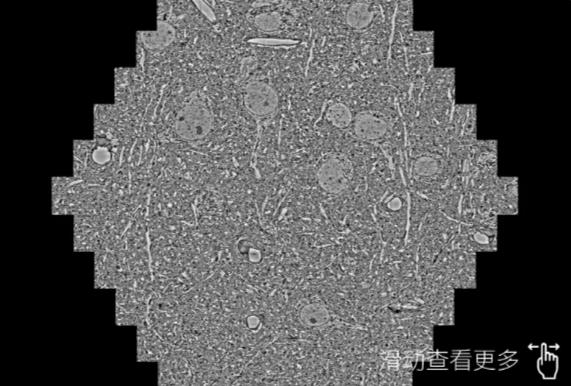

鼠脑切片。左图使用揭阳蔡司揭阳扫描电镜MultiSEM706对165μmx143pm面积区域成像,耗时仅需1.5秒。右图为鼠脑切片中30μm区域放大效果。样品由芝加哥大学B.Kasthuri提供。